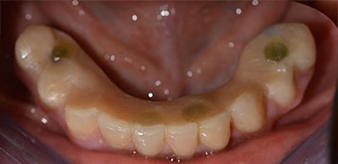

La patiente âgée de 64 ans présente une denture résiduelle des dents 38, 33 et 43 et une prothèse amovible mandibulaire stabilisée par crochets (Fig. 1 et 2).

Dentition résiduelle

Fig. 1

Fig. 2